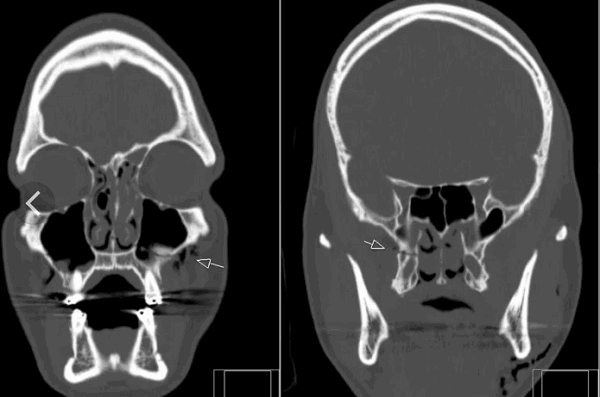

Кости черепа.

По МРТ можно определить перелом костей черепа. Кости свода плоские, видны на МРТ как темная тонкая полоска между кожей и мозговыми оболочками. При обследовании в разных проекциях можно обнаружить линии перелома. Однако они хорошо заметны и при обычной рентгенограмме. Она стоит дешевле и делается быстрее. Зато она не показывает, что происходит с мозгом и оболочками в результате травмы головы. На снимках МРТ можно определить, повреждены ли кроме костей мягкие структуры, есть ли гематомы, разрывы сосудов, очаги некроза, ушиб мозга. При травмах, которые сопровождаются неврологической симптоматикой, методом уточнения состояния головного мозга после перелома станет МРТ.

Перелом основания черепа, височных костей - всегда сложная травма. Она затрагивает множество структур, проходящих между костями, их отростками, внутри полостей. Наиболее полную картину после травмы черепа можно получить именно благодаря томографии на основе магнитного резонанса.